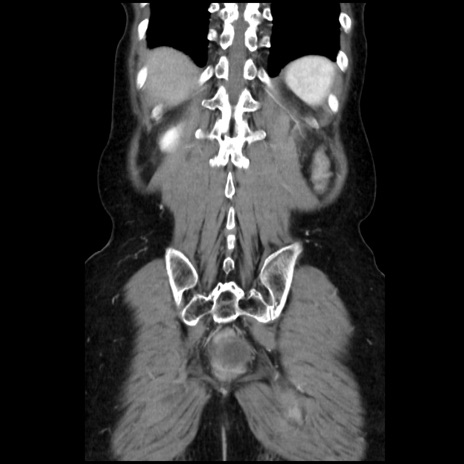

症例32(冠状断像)

【症例】40歳代 女性

【主訴】上腹部痛、嘔気・嘔吐

【現病歴】約9時間前頃から急に上腹部痛、嘔気、嘔吐が出現。改善しないため救急要請。

【既往歴】子宮頚癌(広汎子宮全摘術、放射線療法)、腸閉塞

【身体所見】腹部:平坦、軟、腸雑音亢進、上腹部を中心に腹部全体に圧痛あり。

【データ】WBC 8400、CRP 0.03